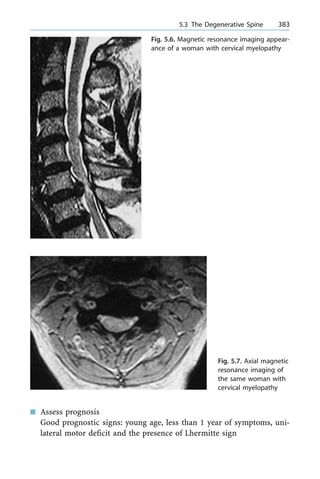

n Effective phase shift

n Energy-efficient fashion